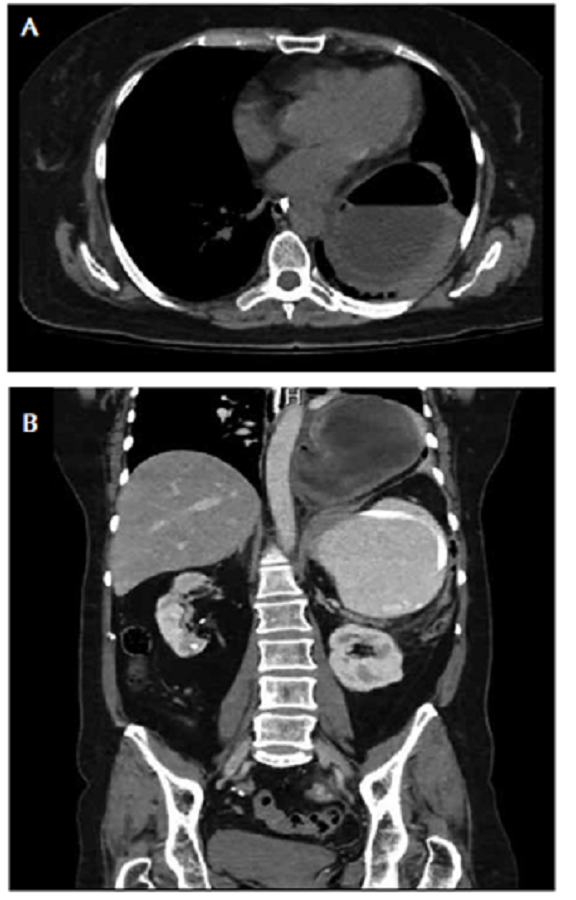

La concentración de la lipasa fue normal. En la TC de abdomen se observó una colección de 95 x 95 mm, con paredes bien definidas, morfología redondeada y contenido hidroaéreo, en la base del hemitórax izquierdo, aparentemente, de localización en el mediastino y extrapulmonar, no dependiente de la pleura, asociada con importante dilatación y aparente obstrucción del estómago a la altura del antro (figura 3, A y B).

Por todo lo anterior, se hizo una impresión diagnóstica de vólvulo gástrico asociado con hernia hiatal y se decidió intervenir quirúrgicamente. Mediante abordaje laparoscópico, se evidenció una hernia hiatal de tipo III (paraesofágica mixta) y vólvulo gástrico mesentéricoaxial, con necrosis y perforación gástrica de 3 cm de diámetro sobre la curvatura mayor en la unión fundocorporal. Se procedió a la reducción de la hernia hiatal y del vólvulo gástrico.